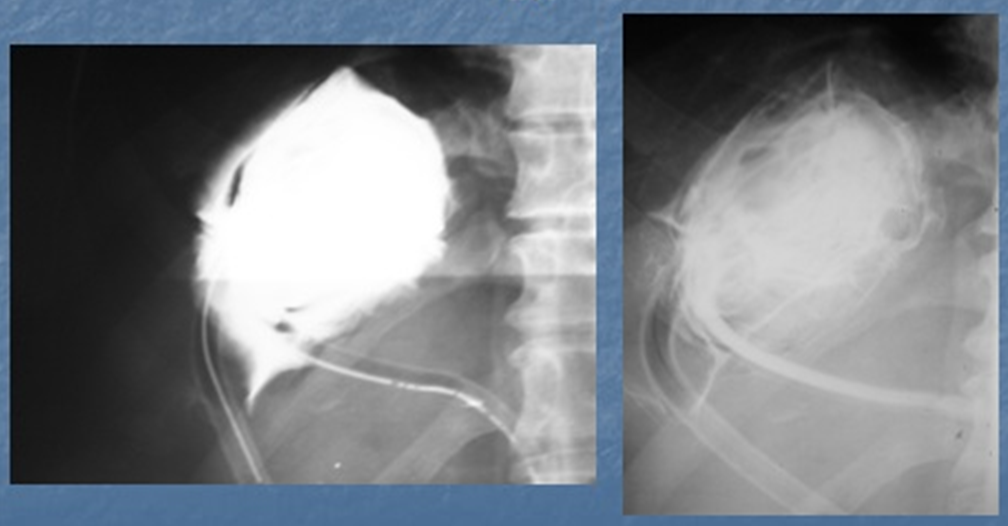

На следующем фото - рентгеновская фистулография подтверждает правильную установку двухпросветных дренажей 9F и 12F в полости эхинококковой кисты, наличие остатков оболочек в полости, отсутствие затеков за пределы кисты в брюшную полость и связи полости кисты с протоками, сосудами и другими органами:

После эвакуации содержимого из полости эхинококковой кисты и выполнения фистулографии, полость кисты неоднократно промыта гипертоническим раствором до чистых вод с полной эвакуацией всех фрагментов оболочек эхинококка:

После этого полость под незначительным давлением наполнена глицерином до восстановления первичного объема кисты. Выдержана экспозиция раствора в полости 15 минут. Затем раствор полностью эвакуирован. При контрольной фистулографии скорректировано положение дренажей в полости (исключающее перегибы дренажей), и дренажи фиксированы к коже швами: